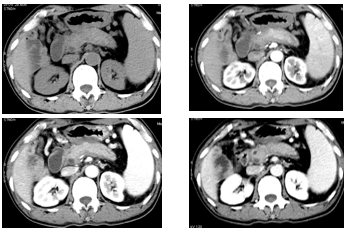

局限性

动态增强 CT 是鉴别胰腺癌和局限性 AIP 的重要手段。

AIP 的低密度肿块在增强早期密度低于周围正常胰腺组织,延迟期则密度均匀一致;而胰腺癌表现为不规则的低密度乏血供肿块,肿瘤远端胰腺萎缩、胰管扩张及周围血管受累。